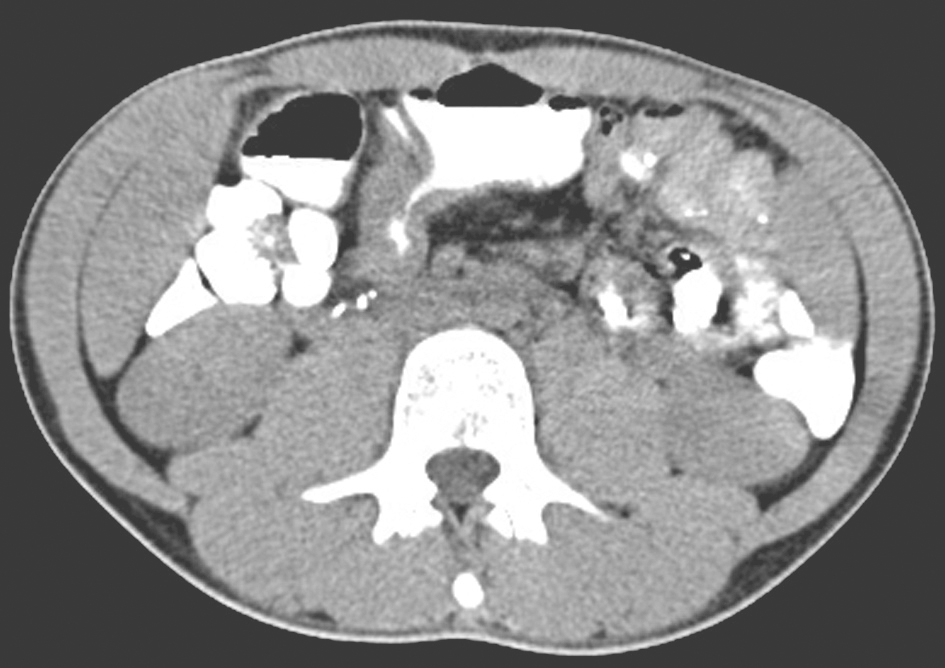

(7)腹部CT

回肠部分肠管扩张,可见异物(胶囊内镜)存留,其近、远端肠管管壁增厚,管腔狭窄,考虑可能为克罗恩病致不全性肠梗阻(图4)。

图4 腹部CT表现